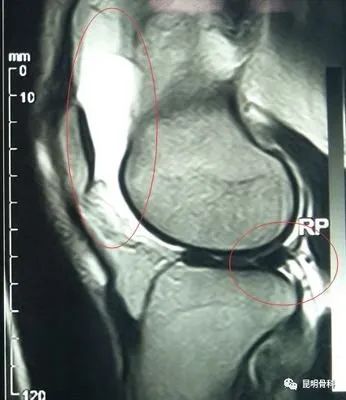

首先建议做膝关节核磁共振检查,一般情况需要卧床休息,下肢抬高,必要时给予下肢支具外固定。膝关节腔积液较多时,可行关节穿刺抽液,并关节注射药物,能够快速缓解关节肿胀疼痛,口服非甾体类消炎镇痛药物,膝关节局部进行膏药外敷、理疗等。